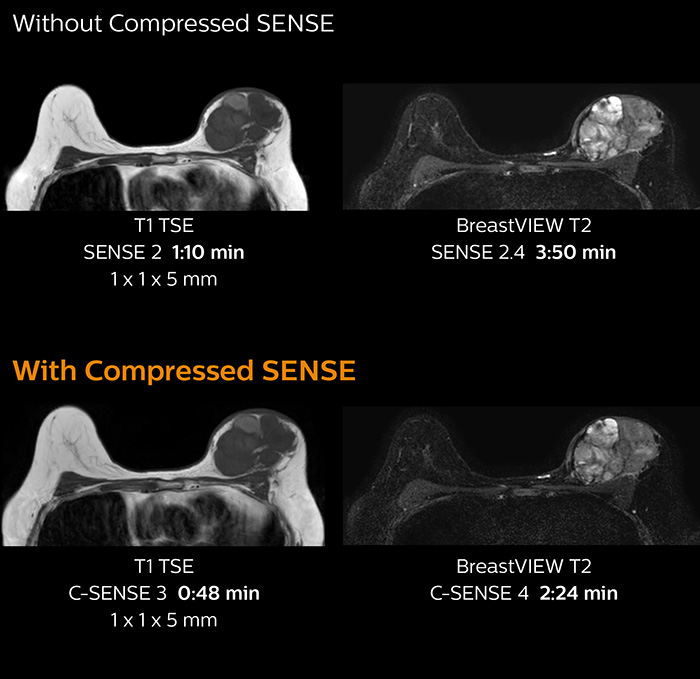

“Compressed SENSE has allowed us to increase spatial resolution in breast MRI, which benefits our diagnostic confidence”

Identification of small breast lesions requires high resolution

“In breast scanning, high resolution is important to help me identify very small mammary lesions, so, we need high spatial resolution in 2D T1- and T2-weighted images, as well as a short scan time. Compressed SENSE has allowed us to increase spatial resolution, which benefits our diagnostic confidence.”

Dr. Koyama says that he used to believe that high resolution MRI at 1.5T required long scan times, and SNR was low. “With Compressed SENSE, however, it is possible to acquire high quality images, even with higher Compressed SENSE factors, so in a quite short time.”

Dr. Koyama says that a C-SENSE factor of 4.0 was chosen to increase their spatial resolution in 3D dynamic breast scanning. “In addition to a high temporal resolution, we also require high spatial resolution, which helps us to see details of the internal structure of the lesion and to see lesions separately from normal anatomic structures. We can also see if a lesion extends into adjacent organs and anatomic structures.”

3D MRI with Compressed SENSE of patient with breast cancer

This patient underwent MRI on Ingenia 1.5T with Compressed SENSE. Compressed SENSE was used to reduce the scan time in order to decrease the time that the patient may experience discomfort and pain, both of which may lead to patient motion. The 3D BreastVIEW and 3D high resolution mDIXON images – both mDIXON contrasts are acquired in the same exam – show high quality images even with the shorter scan time. The spatial resolution of the dynamic scan with Compressed SENSE is higher than in the previous protocol (not shown) which allows for better visualization of the lesion with respect to the muscles of the thoracic wall and better delineation of small structures.

For breast imaging, a fast, high resolution scan can be important for a female patient having to lie in an uncomfortable, face-down position in the scanner. Compressed SENSE also helps us to obtain higher1 quality images using 3D BreastVIEW and 3D high resolution mDIXON sequences in the same examination time as in our previous exam protocol.